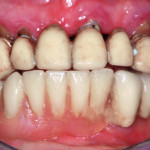

La terapia implantare nel paziente parodontopatico

Riassunto

Nei pazienti affetti da parodontite avanzata ci si trova spesso, alla fine della terapia parodontale, nella necessità di riabilitare dei settori edentuli più o...